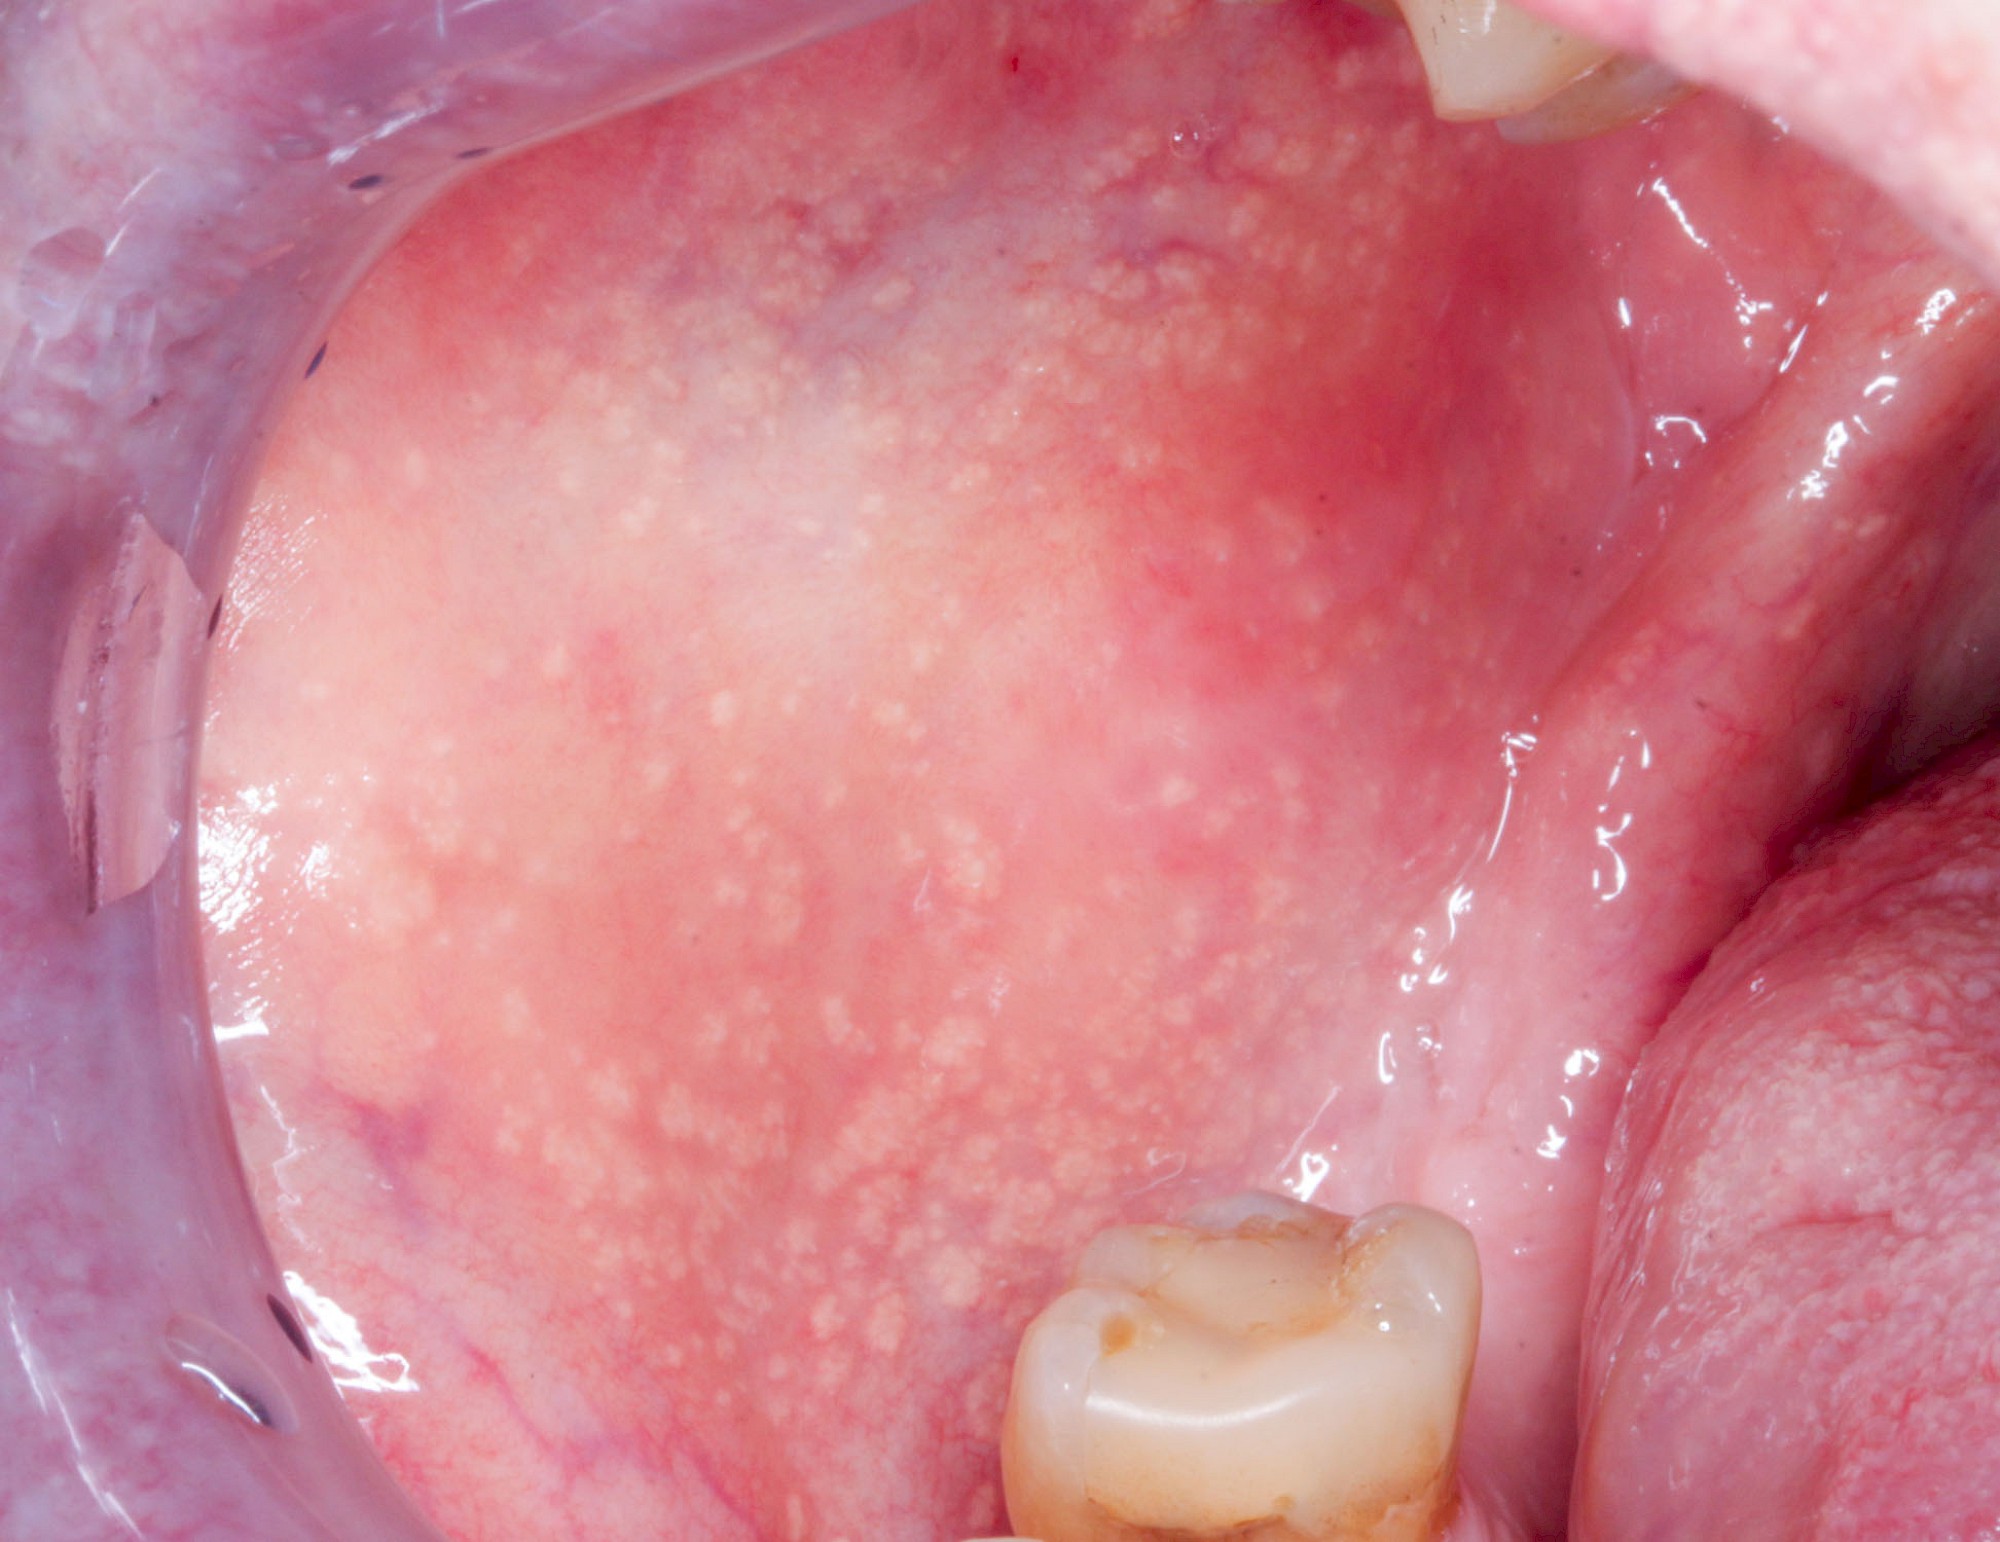

Talgdrüsen

Talgdrüsen sind wichtig für die Haut und machen diese widerstandsfähig gegen Reibungen aller Art. Die Schleimhaut jedoch braucht keine Talgdrüsen, da der Speichel die Oberfläche gut befeuchtet und damit gegen Reibung schützt. Trotzdem kommen – bei manchen Menschen durchaus sehr ausgeprägt – solche ektopen (außerörtlichen) Talgdrüsen vor. Diese haben keinen Krankheitswert und müssen nicht behandelt werden. Ektope Talgdrüsen zeigen sich häufig flächig verteilt und fallen vor allem auf im Bereich der Wangenschleimhaut oder der Lippen.